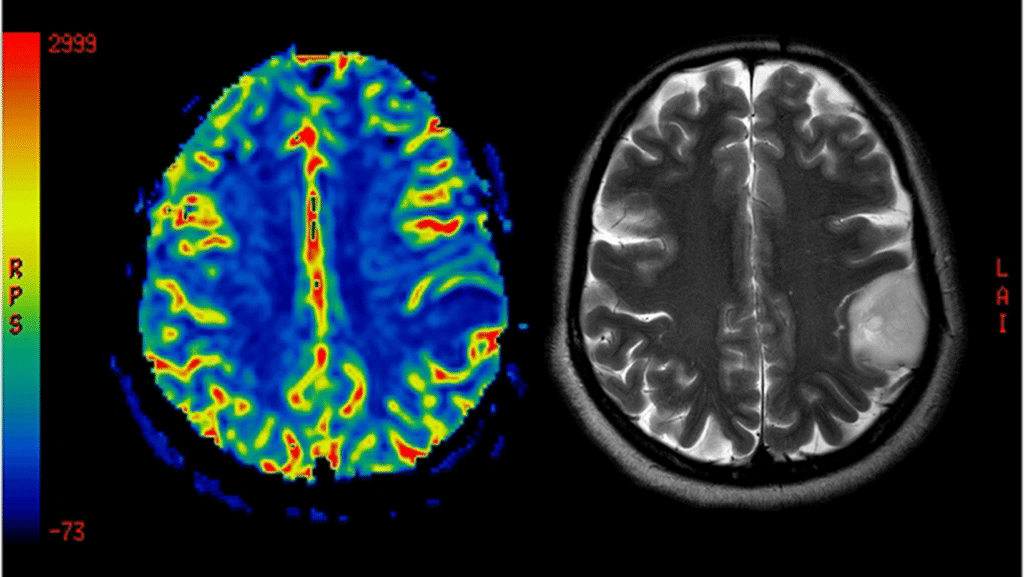

Die Diagnose neurodegenerativer Erkrankungen erfordert oft eine umfassende Untersuchung, einschließlich neurologischer Tests und Bildgebung des Gehirns. Leider gibt es für viele dieser Erkrankungen noch keine Heilung, aber es gibt Behandlungsoptionen, um die Symptome zu lindern und die Lebensqualität zu verbessern.